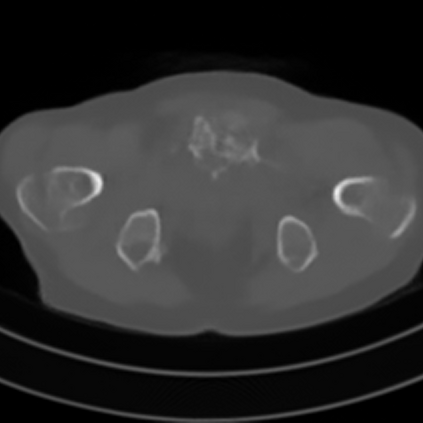

Sparse-view computed tomography (CT) -- using a small number of projections for tomographic reconstruction -- enables much lower radiation dose to patients and accelerated data acquisition. The reconstructed images, however, suffer from strong artifacts, greatly limiting their diagnostic value. Current trends for sparse-view CT turn to the raw data for better information recovery. The resultant dual-domain methods, nonetheless, suffer from secondary artifacts, especially in ultra-sparse view scenarios, and their generalization to other scanners/protocols is greatly limited. A crucial question arises: have the image post-processing methods reached the limit? Our answer is not yet. In this paper, we stick to image post-processing methods due to great flexibility and propose global representation (GloRe) distillation framework for sparse-view CT, termed GloReDi. First, we propose to learn GloRe with Fourier convolution, so each element in GloRe has an image-wide receptive field. Second, unlike methods that only use the full-view images for supervision, we propose to distill GloRe from intermediate-view reconstructed images that are readily available but not explored in previous literature. The success of GloRe distillation is attributed to two key components: representation directional distillation to align the GloRe directions, and band-pass-specific contrastive distillation to gain clinically important details. Extensive experiments demonstrate the superiority of the proposed GloReDi over the state-of-the-art methods, including dual-domain ones. The source code is available at https://github.com/longzilicart/GloReDi.